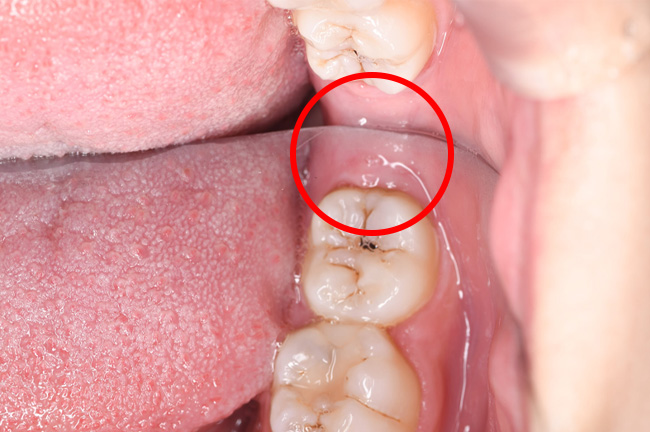

CASE 3

事前にCT撮影を行い神経との位置関係を確認して抜歯を行いました。

頬が被るように親知らずが生えており、歯ブラシが上手くできず虫歯になり歯石もたくさん付いていました。

痛み出血もほとんどありませんでした。

抜歯前

抜歯後

基本情報

| 年齢・性別 | 30代・女性 |

|---|---|

| 主訴 | 右下8/右下の親知らずが痛い |

| 治療内容 | 通常抜歯 |

| 治療期間 | 約30分 |

| 治療費 | 約4,000円 |

| リスク・副作用 | 2〜3日は腫れと痛みがある。 |